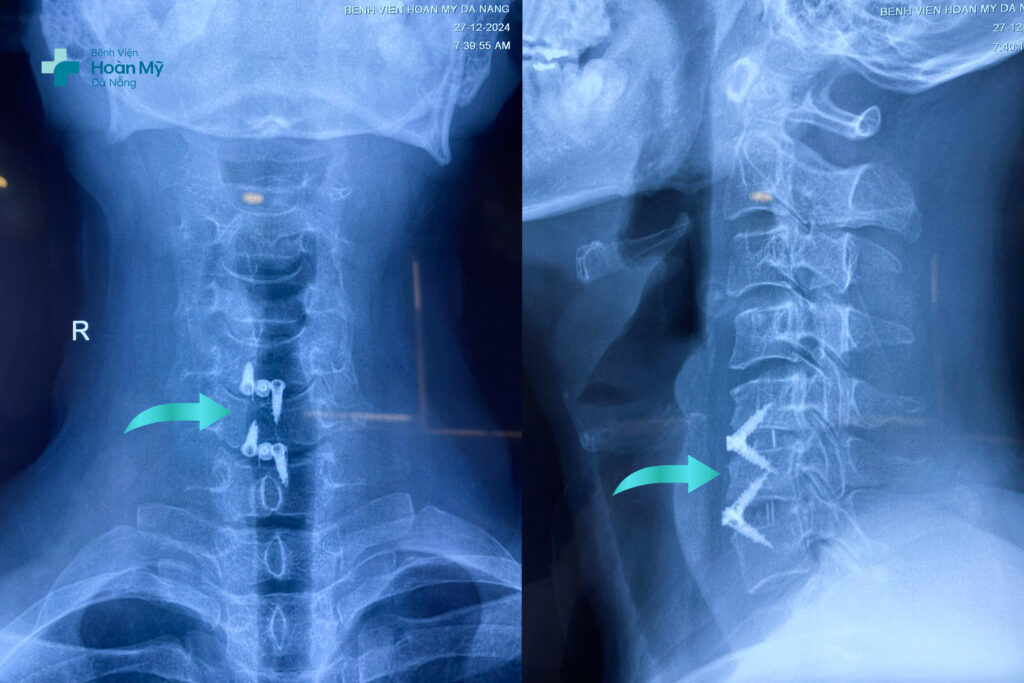

Ca phẫu thuật kéo dài 2 tiếng, ngay sau hồi tỉnh, người bệnh đã có thể cảm nhận được sự cải thiện đáng kể về vận động, cơn đau ở cổ và cánh tay trái gần như biến mất. Và xuất viện sau 5 ngày phẫu thuật.

X-quang về vết hàn xương cột sống bằng phương pháp ACDF trên người bệnh

ACDF là phẫu thuật có độ khó cao và tinh tế đòi hỏi phẫu thuật viên phải có kinh nghiệm chuyên môn sâu, trang thiết bị phòng mổ hiện đại như: kính vi phẫu; màn hình tăng sáng trong phẫu thuật; máy mài cao tốc; hệ thống phòng mổ đạt chuẩn quốc tế giúp phẫu thuật viên quan sát tốt phẫu trường, lấy đĩa đệm thoát vị chèn ép rễ thần kinh và hàn xương cột sống cổ chính xác, kiểm soát tốt các tai biến.